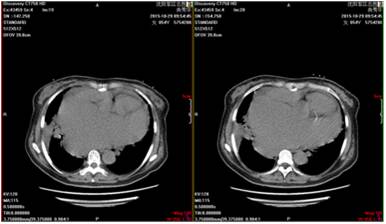

检查日期2015-10-29

左房内径(mm ):92mm

左室舒张末期内径(mm):76mm

右室内径(mm):30 mm

LVEF:47%

超声提示二尖瓣后叶脱垂并重度关闭不全,二尖瓣后叶部分腱索呈“梿枷样”改变,提示二尖瓣后叶部分腱索断裂,三尖瓣中重度关闭不全,肺动脉高压(跨三尖瓣压差 53mmHg),心包积液少量。

肺部CT示右肺下叶基底段见斑片状稍高密度,边界清晰。考虑:考虑右肺下叶炎症,不除外占位性病变。

胸片提示:双肺纹理增强模糊,左侧少量胸腔积液,心胸比0.81。